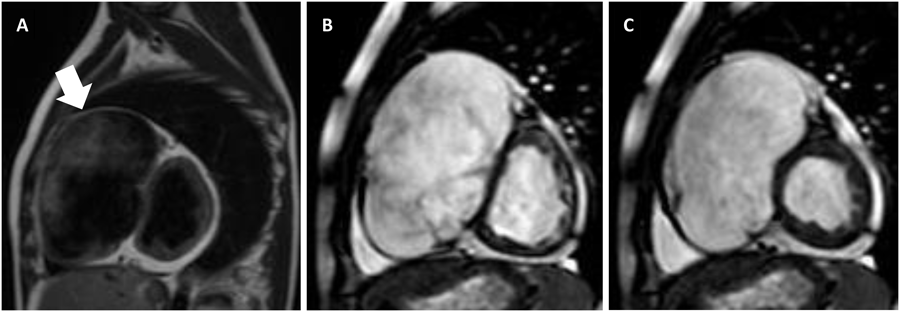

12歳1ヶ月時に施行したMRI(Fig. 4)で左室心筋の菲薄化はなく,左室機能低下を認め(LVEF 44%,Cardiac Output(CO)3.7 L/min),右室自由壁の均一な菲薄化(右室壁厚2 mm),右房拡大と右室拡大(RVEDV 375 mL(377 mL/m2)),右室機能低下(RVEF 13%)を認めた.T1強調画像で催不整脈源性右室心筋症(ARVC: arrhythmogenic right ventricular cardiomyopathy)を示唆する右室心筋の脂肪変性を認めず,MRI上もUhl病として合致する所見であった.15歳1ヶ月時に施行したMRIでは,心室中隔の菲薄化と右室拡大の増悪(RVEDV 538 mL(386 mL/m2))を認めた.両心室機能の悪化はなかった(LVEF 40%, CO 3.8 L/min, RVEF 10%).

Pediatric Cardiology and Cardiac Surgery 32(1): 56-61 (2016)

Fig. 4 Sagittal T1-weighted spin-echo sequence at the age of 12-years showing the almost total absence of right ventricular myocardium and decreased trabeculation (arrow) without fibrofatty replacement (A). Cine magnetic resonance imaging at the age of 15-years showing no right ventricular wall motion and a thinned right ventricular myocardium in comparison to the normal left ventricular myocardium in short-axis view (B: diastolic phase, C: systolic phase)

15歳3ヶ月時のHolter心電図で多源性心房頻拍(MAT: multifocal atrial tachycardia)と診断し,mexiletineに替えてflecainideの内服を開始した.内服開始後,頻拍発作は認めていない.15歳9ヶ月時に心臓カテーテル検査とMRI(Fig. 4)を施行し,右房a波増悪はなく(15 mmHg),両心室機能低下の悪化もなかったが(LVEF 39%, CO 4.1 L/min, RVEF 12%),右室拡大の軽度増悪を認めた(RVEDV 575 mL(394 mL/m2)).

生検に代わって心筋欠如や菲薄化を評価する手段として,非侵襲的な画像診断が可能なMRIが注目されている4, 8, 9).MRIによって比較的簡易に右室心筋の欠如と右室壁の菲薄化をとらえることが可能であり,Uhl病の診断に極めて有効である.GreerらはMRIでのUhl病の特異的所見は,左室心筋に異常を認めず,右室心筋への脂肪浸潤や線維化はなく,右室自由壁心筋欠如と心尖部の肉柱低形成であると報告している4).自験例でもMRIにて右室自由壁の心筋欠如を認め,右室心筋壁厚2 mmと著明な菲薄化と右房と右室の著明な拡張を認めた.拡張する右室を経時的に評価することも可能であり,MRIはUhl病を評価・診断するにあたって非常に有用な検査であると思われる.また,Uhl病の類縁疾患とされるARVCとの鑑別点である右室心筋の脂肪浸潤や線維化をT1強調画像にて認めなかったことから,ARVCを除外診断するにもMRIは有効であった.MRI画像と病理組織所見との比較を論じている文献はなく,自験例もGreerらの報告と同様に生検を実施することなく,MRIにてUhl病の確定診断としている.